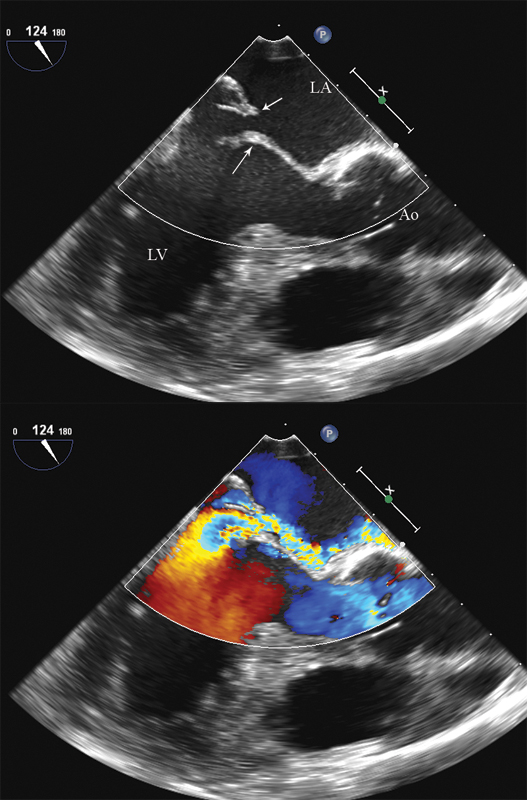

فحوصات تشخيصية لبعض امراض القلب والشرايين التاجية